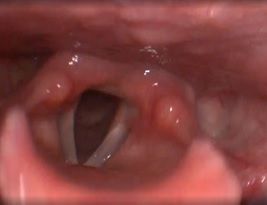

Клинический пример №5. Удаление полипа правой голосовой складки с использованием СО-2 лазера.

После операции, воспалительные проявления со стороны голосовой складки едва заметны.

Рис 5А Полип (отечный) правой голосовой складки. До операции.

Рис 5Б. Полип (отечный) правой голосовой складки. 1 день после операции.